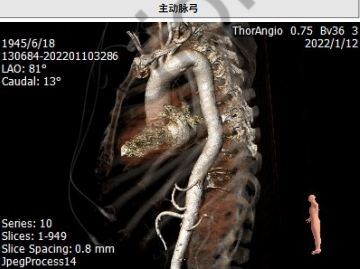

主动脉弓部大折角

入路迂曲

1. 患者为 TypeI型二叶瓣 ,瓣叶增厚,中度钙化。钙化分布不均匀,主要分布瓣叶交界。左冠高度低,瓣叶长,窦宽相对瓣膜可。右冠高度可,瓣叶长,冠脉开口附近在钙化,窦宽相对瓣膜可。

2.主动脉弓迂曲,折角较大,可能会影响瓣膜通过及轴向。

主动脉弓存在团块钙化

大弯侧瓣叶交界存在团块钙化,跨瓣难度较高;主动脉弓存在团块钙化,提升过弓难度。